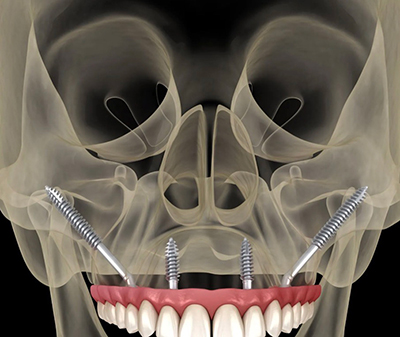

All on 6 dental implants represent a highly customized, biomechanically driven approach to full arch tooth replacement. By using six strategically placed implants, this treatment provides enhanced load distribution, long-term stability, and greater restorative flexibility—especially in complex cases or revision scenarios.

Six implants provide increased surface area, improved force distribution, and greater redundancy—important factors in long-term implant success.

Pterygoid implants anchor into dense bone behind the upper jaw, eliminating the need for sinus grafting in many upper-arch cases. These implants provide posterior support where bone is often lacking.

Transnasal implants engage dense nasal floor bone to stabilize upper arch restorations in patients with advanced bone loss. This technique is especially valuable in revision cases and complex maxillary anatomy.